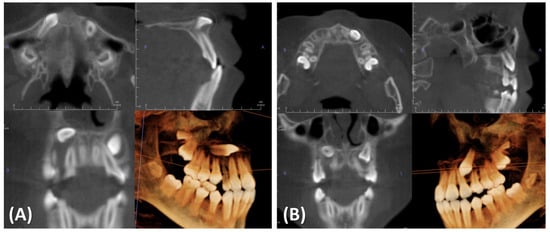

2. Case Presentation

2.1. Diagnosis and Etiology

2.4. Treatment Progress